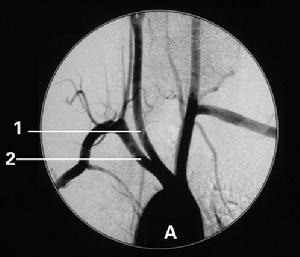

2、大面積腦梗死臨床腦CT掃描腦MRI檢查顯示大面積腦梗死以及梗死後大範圍水腫是出血性腦梗死的危險因素。大面積腦梗死好發於顱底Willis環的前半部分,栓塞面積按Pullicino計算法15ml以上為大面積栓塞。大面積腦梗死時常伴有明顯的腦水腫,使周圍血管受壓,血液淤滯,水腫消退後水腫壓迫損傷的血管重新灌注因長時間缺血缺氧腦血管通透性增強易發生滲血及出血。

出血性腦梗死造影2、根據出血性腦梗死的發生時間分兩型

出血性腦梗死2、影像學檢查腦CT掃描或MRI檢查等影像學檢查提示出血性梗死。